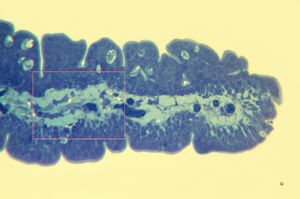

Methylene-blue-stained epoxy-resin semithin section of intestinal unmyelinated vegetative nerve (left)and ganglion cells of plexus submucosus Meissneri (right). (Human, small intestine.)